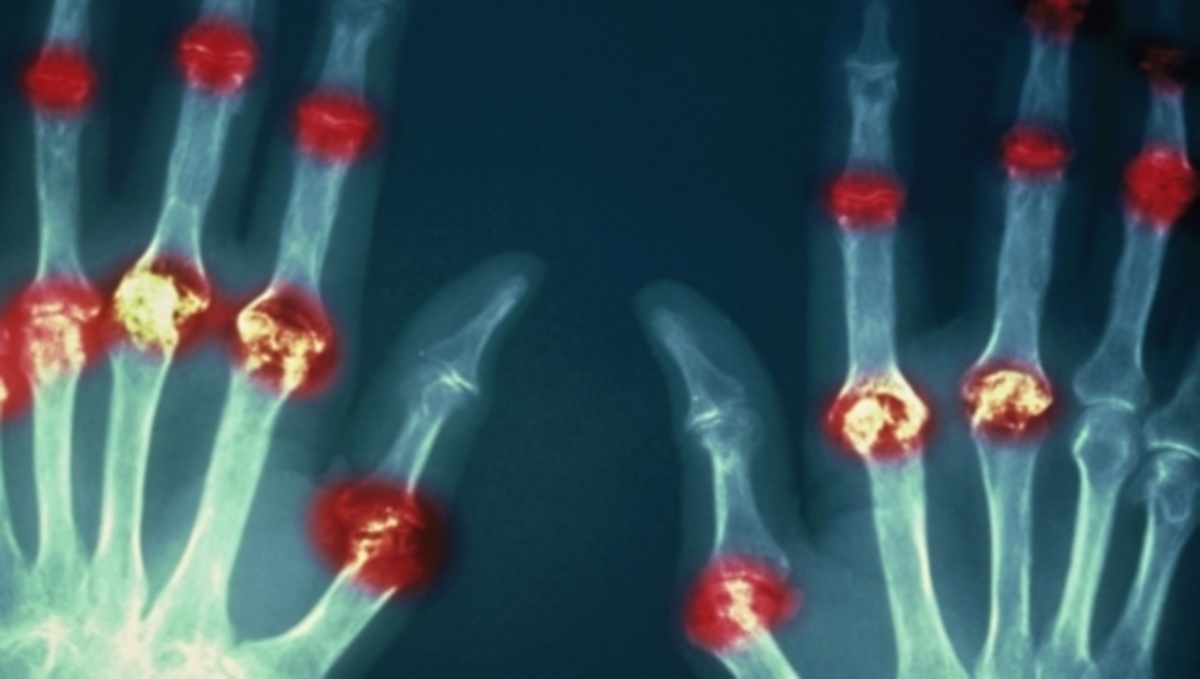

Τι να τρώτε για να μειώσετε άμεσα το ουρικό οξύ – Κίνδυνος ουρικής αρθρίτιδας

Το ουρικό οξύ παράγεται όταν το σώμα διασπά μια χημική ουσία που ονομάζεται πουρίνη. Η πουρίνης εμφανίζεται υπάρχει φυσικά στο σώμα σας, αλλά εμπεριέχεται επίσης σε ορισμένες τροφές. Το ουρικό οξύ αποβάλλεται από το σώμα με τα ούρα.